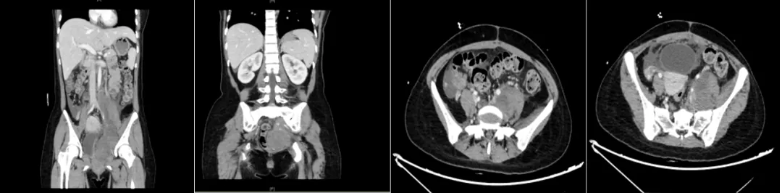

图1:2012年腹部CT平扫+增强:左中下腹部见巨大囊实性肿块影,大部分呈囊性,CT值约14一27HU,大小约11.4cmX7.1cmX14.1cm,部分囊壁见少许钙化灶。增强后囊壁及实性部分轻度强化。邻近左肾、肠管、血管部分受压、移位。病灶周围未见明显肿大淋巴结。其下方另盆腔偏左侧可见多房状类似病灶,大小约13.4cmX8.4cm×13.8cm